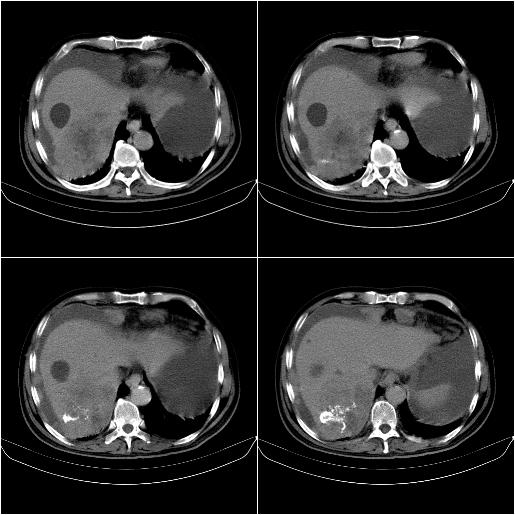

m,67y,肝癌9月,介入术后3月。现腹胀、纳差、腹泻。

1)肝癌介入治疗术后碘油沉积不良。2)门静脉瘤栓形成,腹膜广泛性转移。3)肝硬化,脾大,腹水。4)慢性胆囊炎。